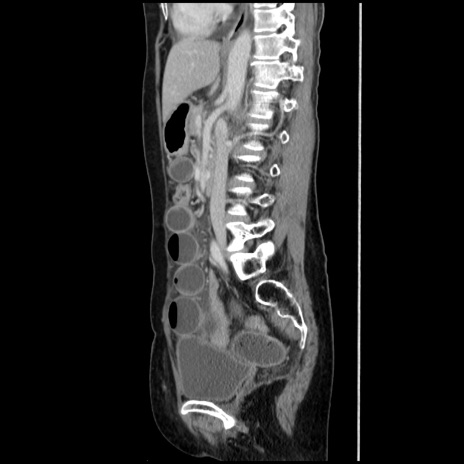

症例32(矢状断像)

【症例】40歳代 女性

【主訴】上腹部痛、嘔気・嘔吐

【現病歴】約9時間前頃から急に上腹部痛、嘔気、嘔吐が出現。改善しないため救急要請。

【既往歴】子宮頚癌(広汎子宮全摘術、放射線療法)、腸閉塞

【身体所見】腹部:平坦、軟、腸雑音亢進、上腹部を中心に腹部全体に圧痛あり。

【データ】WBC 8400、CRP 0.03